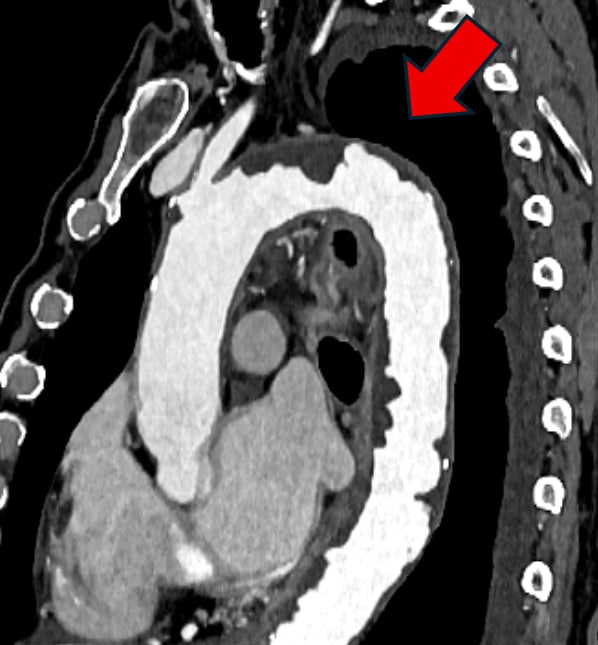

図2.大動脈造影CT MPR像

弓部から下行大動脈に、内腔側へ不整に突出する粥腫を連続性に認める(→)。一部で表面不整や小陥凹を伴い、shaggy aortaとして術中塞栓リスク評価上の重要所見。